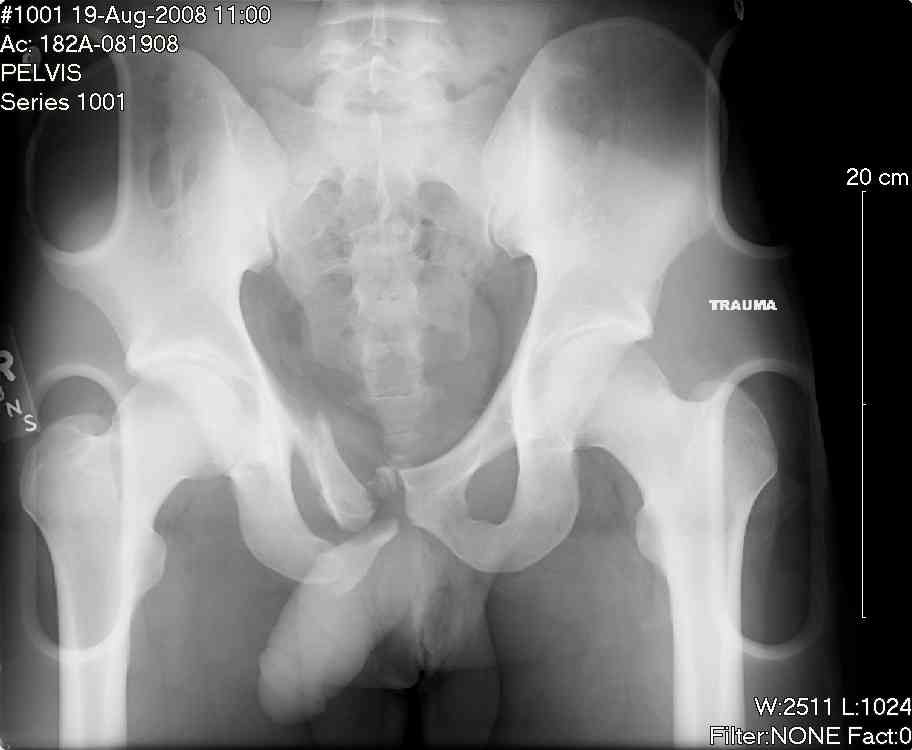

hello,this is a healthy 22yo male. peds vs auto.

no other injuries. has anyone treated these non-operatively? thanks.

It's type A pelvic-ring lesions. Because

the pelvic ring is stable, it

cannot be displaced by physiologic

forces and may be treated non-operativly in male.

One bit of important yet omitted info is the patient's physical exam... if this pelvic ring injury is unstable to exam, then I'd recommend operative reduction and stable fixation to him.